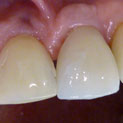

En estos casos han sido tratados con la filosofía de all-at-once, en la

misma sesión: